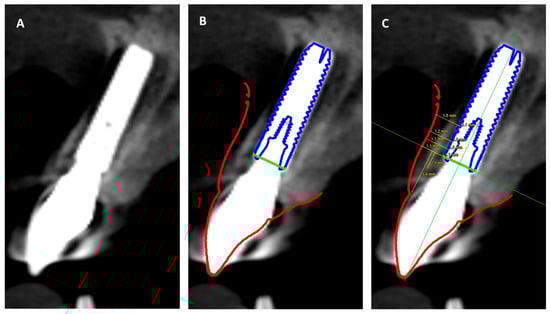

2. Materials and Methods

| Implant Shoulder | 1 mm | 2 mm | 4 mm | Mean Thickness | |

|---|---|---|---|---|---|

| Bone | 1.7 | 1.5 | 1.5 | 1.1 | 1.45 |

| Soft tissue | 1.1 | 1.1 | 1.2 | 1.8 | 1.3 |

| Combined tissue thickness | 2.8 | 2.6 | 2.7 | 2.9 | 2.75 |